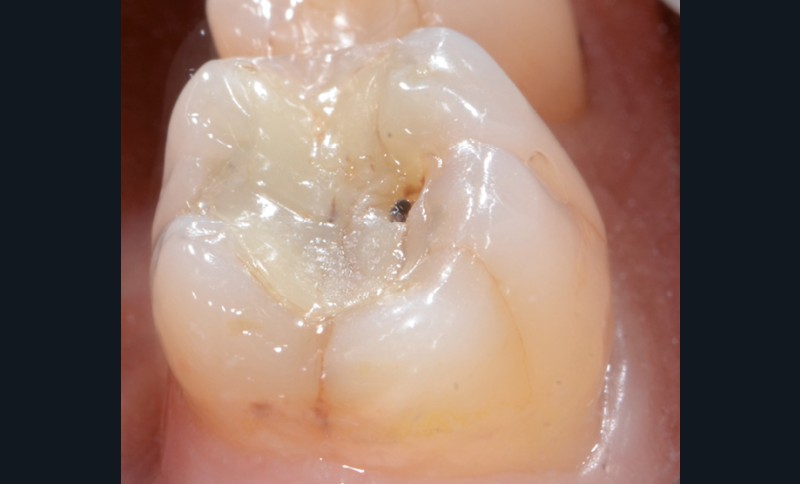

1 et 2. Un patient se présente à la consultation en raison d’une 36 douloureuse à la pression. La présence d’un inlay composite occluso-mésial ancien, infiltré, et des joints défectueux est constatée. L’analyse biomécanique révèle des fêlures, surtout au niveau de la crête marginale distale. Il faut de plus noter l’absence de la 37. Il est donc décidé de déposer la restauration et de réaliser un overlay en vitrocéramique de type e.max (Ivoclar Vivadent).